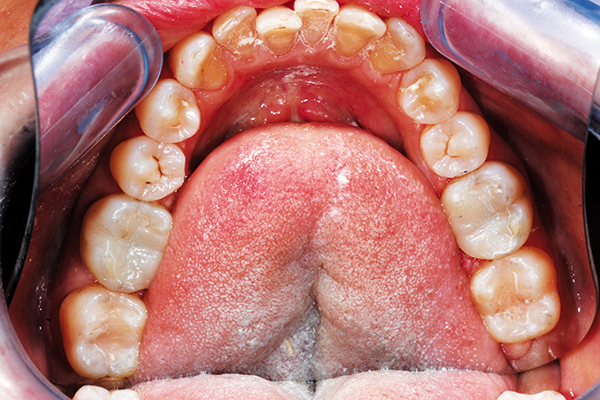

A middle-aged patient presented with a desire for a healthier, more youthful smile that was compromised by crowding and wear. A conservative approach of ABB (alignment, bleaching and bonding) was recommended, starting with aligner care with Invisalign (Fig. 1).

Fig. 1 Fig. 2

Post-orthodontic care wasn’t rushed to establish solid tooth positions and occlusion. This involves three months of retention along with deprogramming, whitening and equilibration at the end. (Fig. 2).